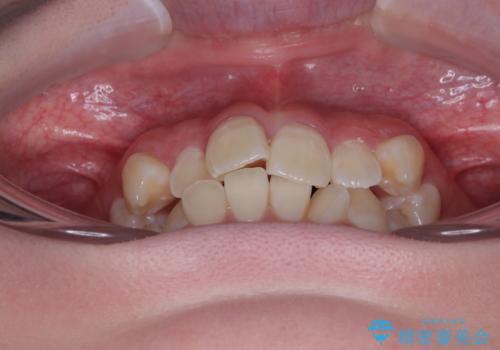

- 「前歯のデコボコ(叢生)をきれいに整えたい」とのことでご来院されました。

上下の正中(真ん中のライン)もずれることなく、バランスの取れた美しい歯並びに。笑顔に自信を持てる仕上がりとなりました。